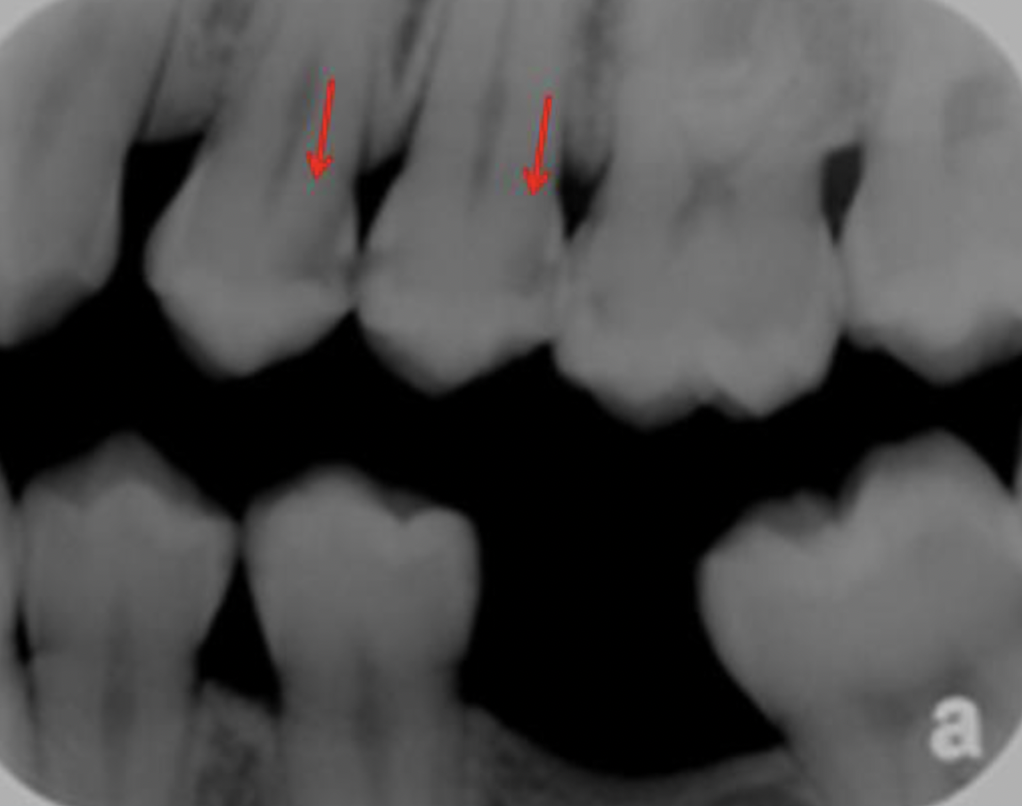

68

What is going on in the following radiograph?

Interproximal burn out